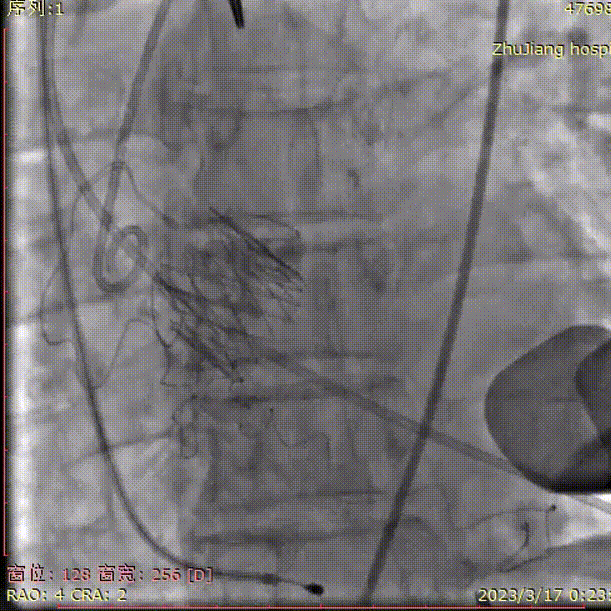

复查根部造影,未见明显反流:

术后血压103/60mmHg,即刻行食道超声,主动脉瓣口可见生物置换瓣回声,启闭正常;Vmax 2.0m/s, PGmax 16mmHg;瓣周未见分流: